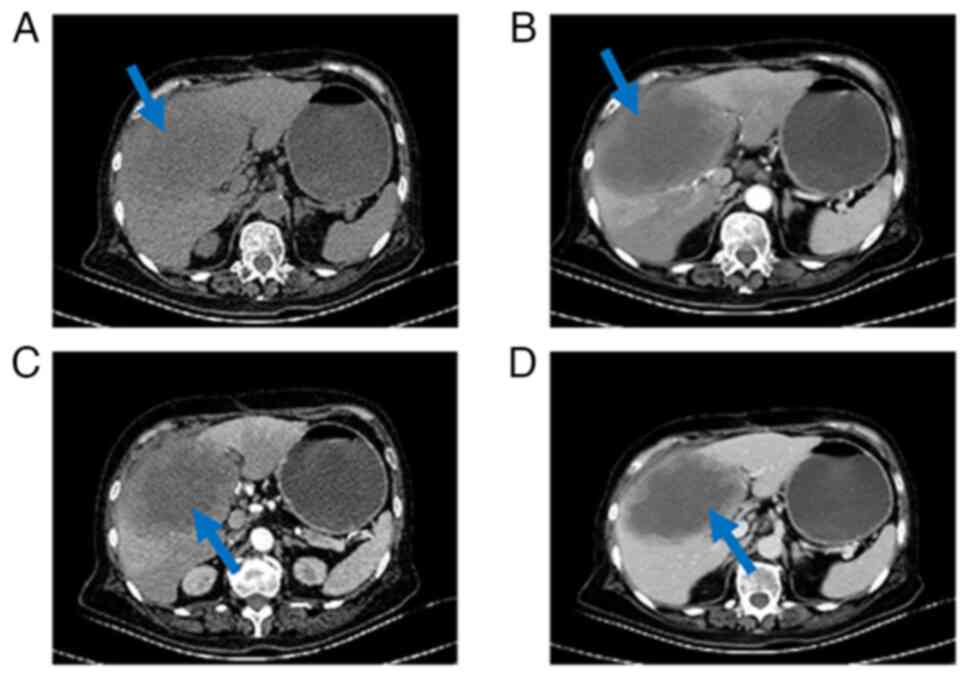

Following the collection and analysis of blood specimens, postoperative tumor marker reassessments provided the following results (Table I). A total of 40 days postoperatively, CEA and CA 19–9 levels returned to the normal range. However, during the 90-day follow-up, both markers showed an increase. By contrast, AFP remained within the normal range both preoperatively and postoperatively. After the observed increase in tumor marker levels, a comprehensive abdominal contrast CT scan was performed 100 days post-surgery (Fig. 4). A large occupying lesion in the surgical area, measuring ~12×8 cm was observed. The enhancement scan revealed rim and nodular enhancement at the periphery with no central enhancement.

Figure 4.

CT scan images of the patient, 100 days post-surgery. (A) Right lobe of the liver showed a slightly low-density shadow and an unclear edge of the lesion in the surgical area (blue arrow). (B) In the arterial phase, significant enhancement can be observed in the lesion (blue arrow), while there are focal and patchy areas of obvious enhancement at the periphery of the lesion. No enhancement is observed in the central low-density area of the lesion. (C) The details of arterial phase thin-layer lesions (blue arrow) are displayed more clearly. (D) In the portal venous phase, evident enhancement can still be observed in the lesion (blue arrow), and the solid enhancing component at the periphery of the lesion shows an increased range compared with the arterial phase, but no enhancement was found in the central low-density area.